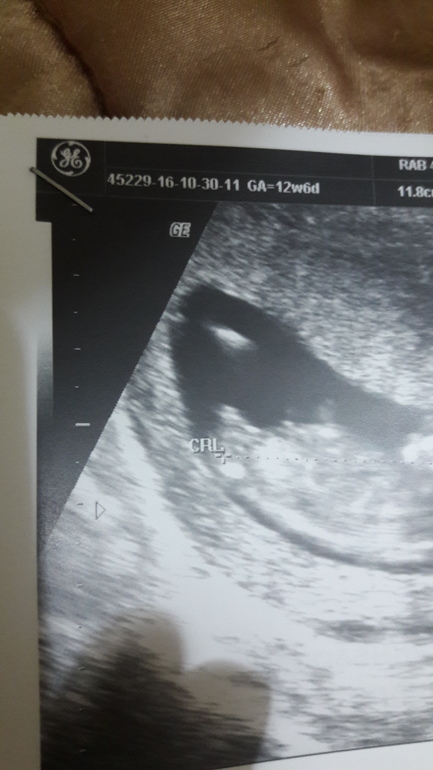

УЗИ, КТГ, доплерПо УЗИ срок 12 недель и 6 дней

выглядит, прям как мой малыш)

но тут трудно определить кто, узистка даже не взялась, сразу сказала, что приходите хотя бы после 16 недельки, там уже виднее будет)